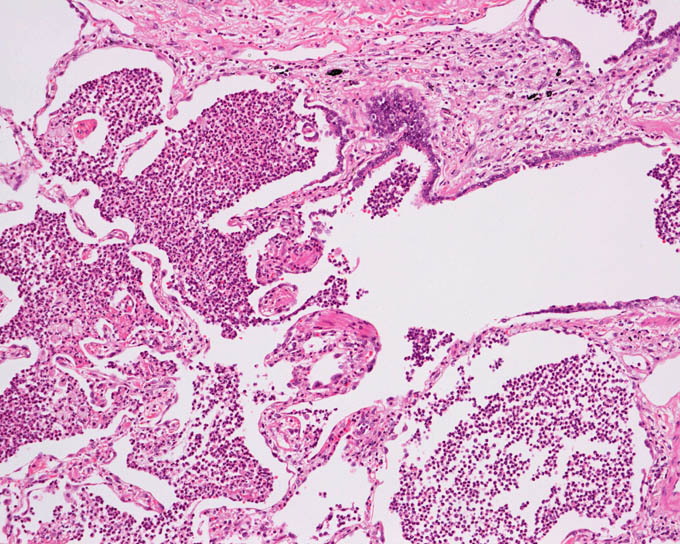

呼吸器

気管支肺炎